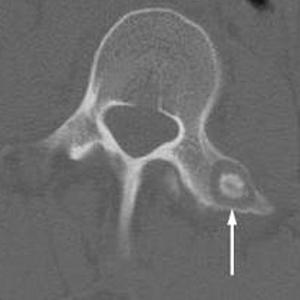

Остеома определяется на основе рентгеновского снимка затронутых костей. Для более глубокого анализа врач может назначить компьютерную томографию, которая позволяет точно определить местоположение опухоли и ее характеристики.

На этом рентгеновском снимке четко демонстрируется расположение опухоли: